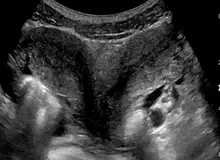

پزشکان میگویند یک زن ۳۲ ساله اهل آلاباما در آمریکا که یک جفت رحم در بدن دارد، در هر دوی آنها باردار شده است. این پدیده به حدی نادر است که تقریبا تمامی متخصصان زنان و زایمان در طول حرفه طبابت خود با چنین موردی روبرو نمیشوند